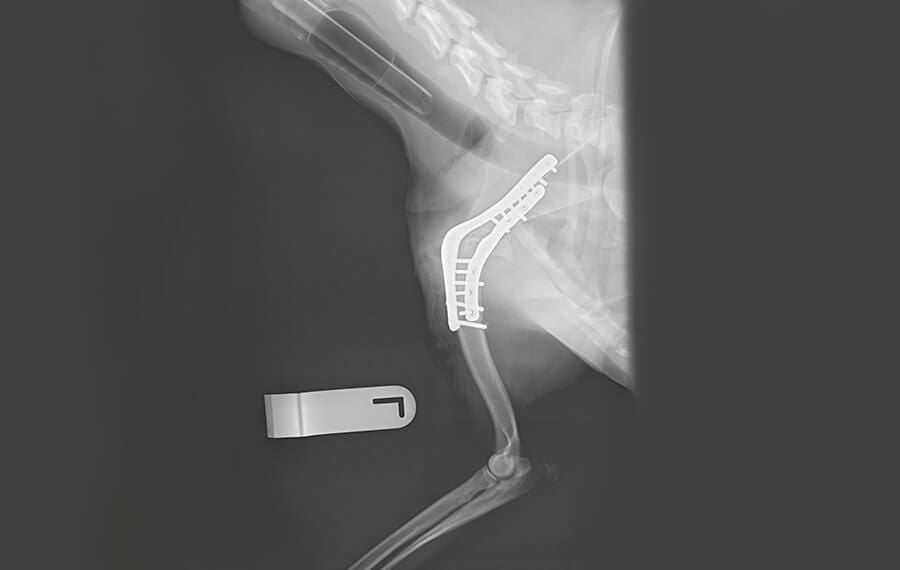

Shoulder Arthrodesis (fusion of the shoulder)

Fusion of the scapulohumeral joint (where the shoulder blade meets the upper arm bone).

- Function: This procedure has a more pronounced effect on gait than lower-limb fusions. Because the shoulder is now fixed, the pet moves the limb using the muscles that rotate the shoulder blade (scapula) against the chest wall. While the gait has a "mechanical" swing to it, it allows for comfortable, weight-bearing movement.

- Indications: Typically reserved for chronic, non-reducible shoulder dislocations (luxations), severe instability, glenoid dysplasia or end-stage osteoarthritis.